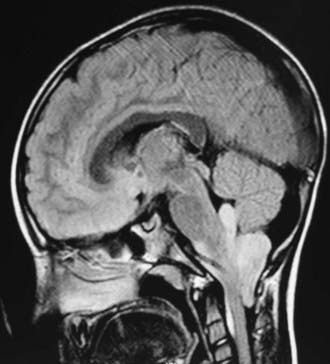

中枢神经系统(CNS)肿瘤多发于儿童,在组织学和肿瘤部位上与成人有很大差异。与大多数中枢神经系统肿瘤位于幕上的成年人相比,约50%至55%的儿童中枢神经系统肿瘤位于幕下。在6个月大的时候,幕上肿瘤更常见;然而,到了2岁,这种位置就会逆转,60%的人会出现幕下症状。这与生命的三个十年及以后形成对比,那时只有25%到35%的颅内肿瘤是幕下肿瘤。

神经系统的细胞大致可分为神经细胞和称为神经胶质的多种支持细胞。胶质细胞的数目大大超过神经细胞,约为3:1,其中包括星形胶质细胞、少突胶质细胞、室管膜细胞和小胶质细胞。总的来说,胶质瘤,更确切地说,星形细胞瘤是儿童常见的中枢神经系统肿瘤,在某些系列中占高达50%。星形细胞瘤在组织学、细胞学和行为特征上有很大的差异,并且在儿童人群的几个地方都有发生。毛细胞性星形细胞瘤是常见的,约占儿童中枢神经系统肿瘤的25%。这些肿瘤被认为是良性的,通常发生在后颅窝,但也可以在其他地方发现。然而,儿童神经胶质瘤的其他常见部位包括下丘脑和视神经通路区域。这些病变的组织学通常是低等级的,但由于它们的位置,很难手术治疗。脑干胶质瘤是一种弥漫性浸润性肿瘤,其自然史和预后不良与多形性胶质母细胞瘤相似,是成人常见的原发性幕上肿瘤。脑干局灶性病变的预后可能更好,可以通过磁共振成像(MRI)的连续监测进行监测。脑干的其他局灶性病变可能有背侧外生部分,适合手术切除。